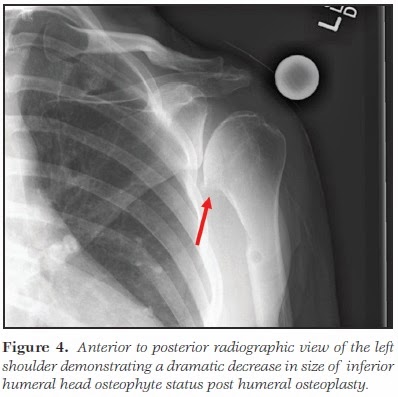

| Joelho de feto com 16 semanas. LFC: côndilo femoral lateral; LM: menisco lateral; PL: feixe postero-lateral do LCA; AM: feixe antero-medial do LCA; MFC: côndilo femoral medial; MM: menisco medial |